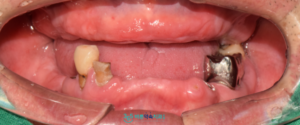

먼저 구강 내 상태를

확인해 보았더니,

다수 치아가 상실되어 있었으며,

잔존 치아들도 충치와 잇몸 질환으로 인해

예후가 좋지 않았습니다.

정밀한 진단을 위해

파노라마 사진을 촬영한 결과,

남아 있던 치아들은

모두 심한 잇몸 질환의 영향을 받고 있었고,

치아를 지지하는 잇몸 조직도

많이 약해진 상태였습니다.

또한 치아의 흔들림도

큰 편이어서 발치가 불가피한 상황으로

판단되었습니다.